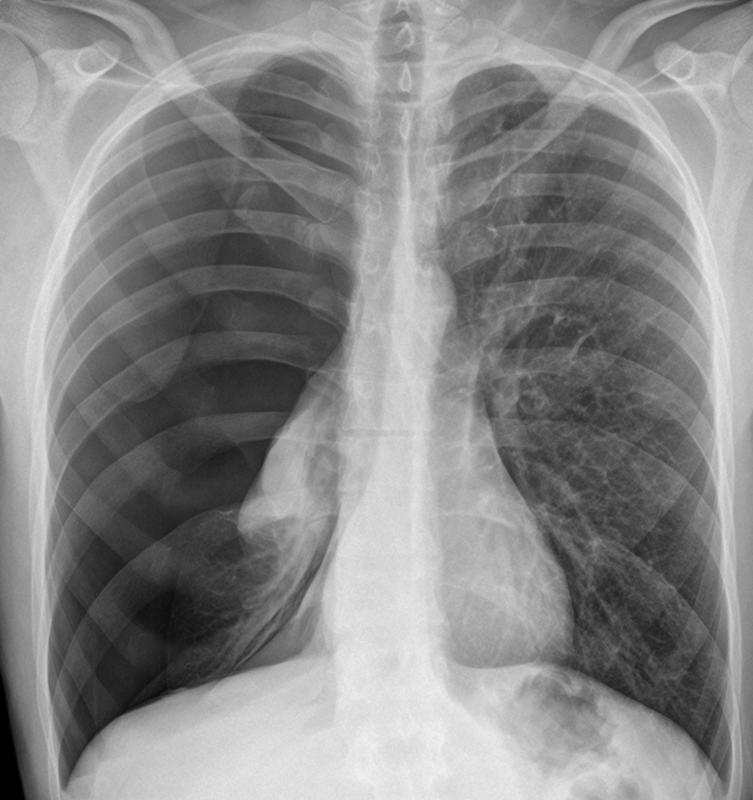

Gallery Pleural Complete pneumo-slight tension

Complete pneumo-slight tension